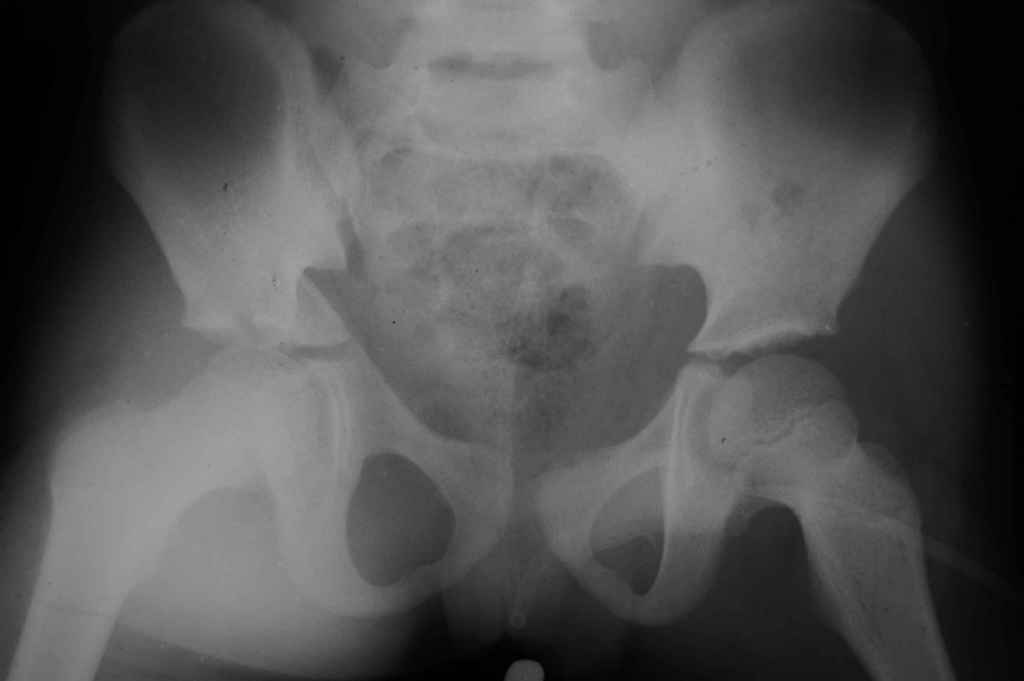

Перелом вертлужной впадины

Уважаемые коллеги, помогите определиться с тактикой лечения. Ребёнок 7 лет, травма 11.09.08, поступил с травматическим вывихом бедренной кости.

Вывих вправлен, конечность фиксирована на скелетном вытяжении. Что делать с переломом подвздошной кости? Лечить консерватино или оперировать?